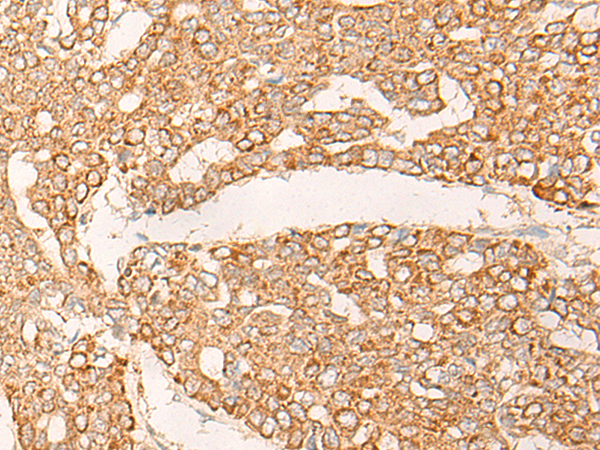

IHC positive control: |

Human liver cancer and Human gastric cancer |

IHC Recommend dilution: |

30-150 |